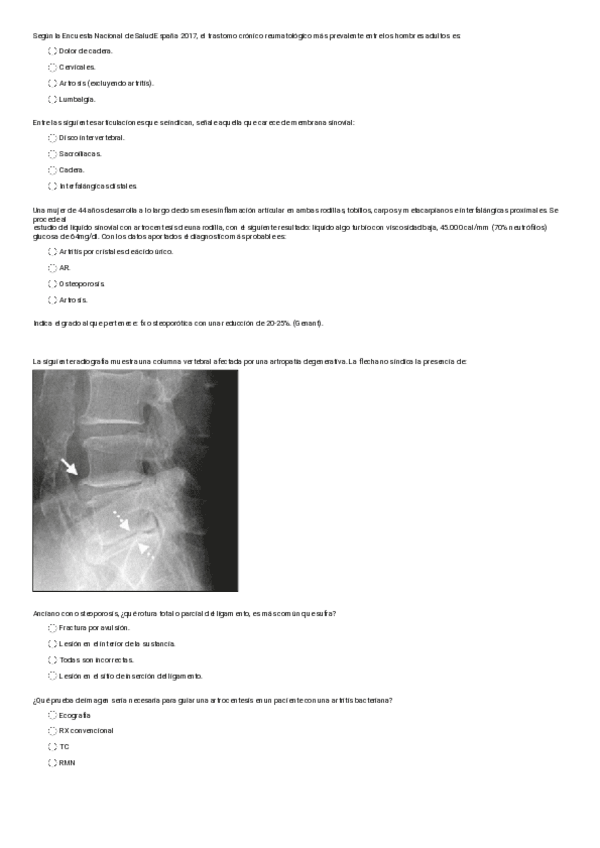

He publicado nuevos ejercicios de 2º Cuidados de Enfermería en Procesos Osteoarticulares: radiografias.pdf

2 páginas